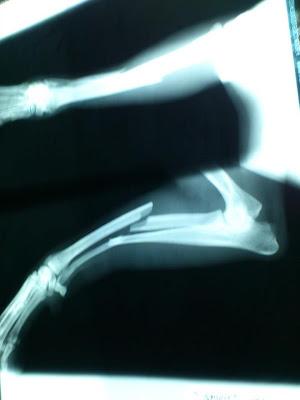

Tiene una fractura en cúbito y radio, es positivo en leishmania, sus orejas están reventadas y su boca destrozada, tiene los dientes como separados de la encía... le han puesto ya un tratamiento y deben hacerle curas. La veterinaria que lo ha atendido dice que la lesión de la boca seguramente haya sido causada por una fuerte patada o un golpe.

Queremos pensar que Spirit saldrá adelante, aunque quizás requiera operación en su pata para que camine bien y suelde sin ocasionarle más daños.